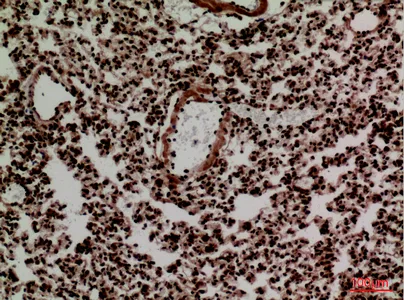

MPO Rabbit Polyclonal Antibody

Cat: APRab14056

Size1:50μl Price1:$118

Size2:100μl Price2:$220

Size3:500μl Price3:$980

Size2:100μl Price2:$220

Size3:500μl Price3:$980